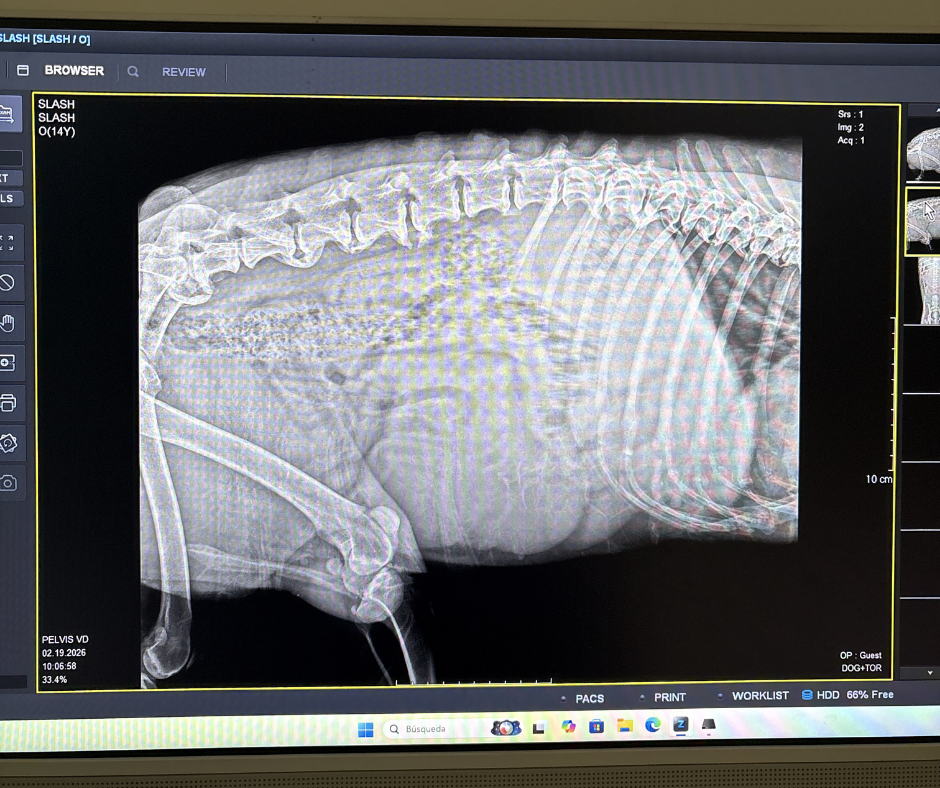

La columna está formada por vértebras separadas por discos. Con el paso del tiempo, el desgaste o microlesiones, el cuerpo intenta “estabilizar” la zona. Para hacerlo, empieza a formar hueso extra en los bordes de las vértebras. Ese hueso crece poco a poco hasta que une una vértebra con otra, formando lo que en la placa se ve como un “puente”.

Radiografia puentes